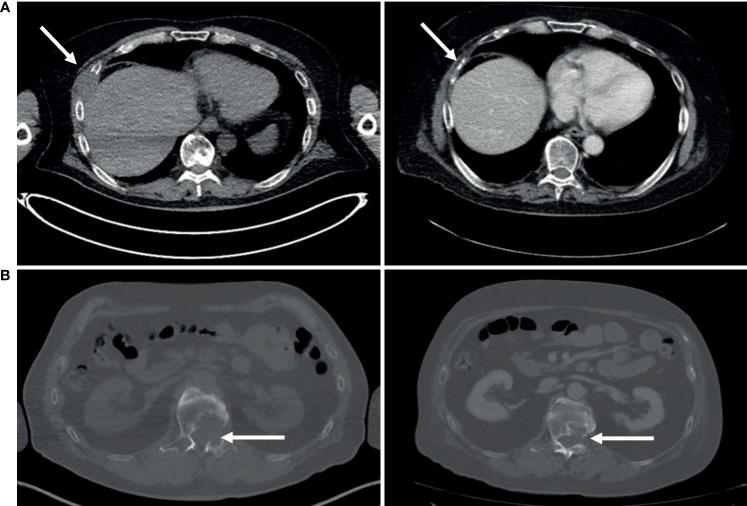

The purpose of drug screening in the context of precision oncology is to serve as a functional diagnostic method for therapy efficacy modeling directly on patient-derived tumor cells. Here, we report a case study using integrated multiomics drug screening approach to assess therapy efficacy in a rare metastatic squamous cell carcinoma of the parotid gland. Tumor cells isolated from lymph node metastasis and distal subcutaneous metastasis were used for imaging-based single-cell resolution drug screening and reverse-phase protein array-based drug screening assays to inform the treatment strategy after standard therapeutic options had been exhausted. The drug targets discovered on the basis of the measured drug efficacy were validated with histopathology, genomic profiling, and cell biology methods, and targeted treatments with durable clinical responses were achieved. These results demonstrate the use of serial drug screening to inform adjuvant therapy options prior to and during treatment and highlight HER2 as a potential therapy target also in metastatic squamous cell carcinoma of the salivary glands.

在精准肿瘤学背景下进行药物筛选的目的是作为一种功能诊断方法,直接在患者来源的肿瘤细胞上建立治疗疗效模型。在此,我们报告一项病例研究,该研究使用综合多组学药物筛选方法评估腮腺罕见转移性鳞状细胞癌的治疗疗效。从淋巴结转移灶和远处皮下转移灶分离出的肿瘤细胞用于基于成像的单细胞分辨率药物筛选和基于反相蛋白阵列的药物筛选试验,以便在标准治疗方案用尽后为治疗策略提供参考。基于测得的药物疗效发现的药物靶点通过组织病理学、基因组分析和细胞生物学方法进行验证,并实现了具有持久临床反应的靶向治疗。这些结果证明了使用系列药物筛选在治疗前和治疗期间为辅助治疗方案提供参考,并突出了HER2作为唾液腺转移性鳞状细胞癌潜在治疗靶点的作用。